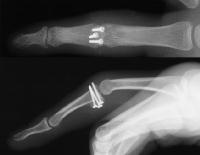

Here, the graft is in place and the joint has been reduced. The proximal two screws were then backed out slightly, and the volar plate was secured with sutures looped around the proximal two screws, which were then tightened back (not shown).

Final reconstruction.